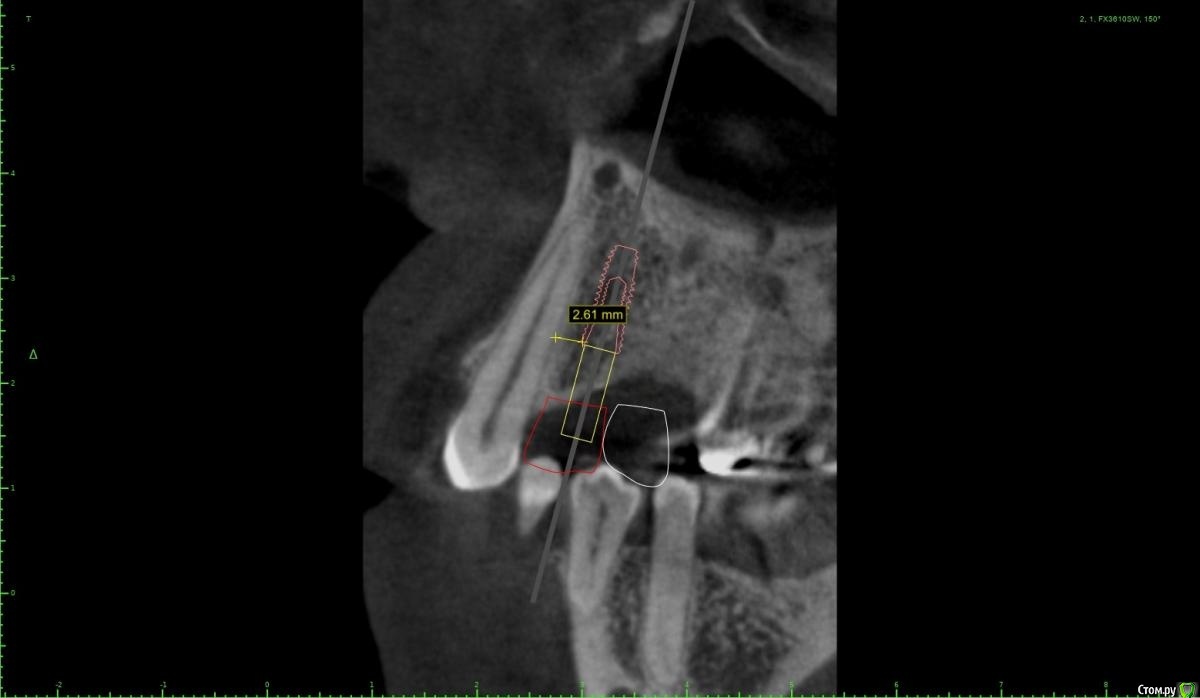

Женька Опубликовано 28 января, 2021 Поделиться Опубликовано 28 января, 2021 Что-то все спрашивают про консоли на имплантатах в области премоляров! Спрошу и я тоже.Коллеги как бы поступили в этом случае?Сам склоняюсь к консоли, но переживаю, что надо бы имплантат пошире, чтобы нагрузку нёс за двоих спокойно. Вариант с двумя винтами не нравится потому как тонковато (не очень) в области 1.4 и необходима редукция около 3мм кости. Ссылка на комментарий

Женька Опубликовано 1 февраля, 2021 Автор Поделиться Опубликовано 1 февраля, 2021 ИМХО два винта, но давайте с замерами тогдаДа, наверное вы правы, два по 3.6 проходят Ссылка на комментарий

Irouil Опубликовано 1 февраля, 2021 Поделиться Опубликовано 1 февраля, 2021 Я бы развел винты побольше, лучше ближе к зубам чем друг к другу, кроме того дистальный имплант можно сместить немного небнее Ссылка на комментарий

колесников Опубликовано 2 февраля, 2021 Поделиться Опубликовано 2 февраля, 2021 Два прекрасно проходят. Лучше имплант не агрессивный с микрорезьбой 3.5х8. Редуцировать грибком из набора даск. 14 сст вестибулярно и нагрузка на оба. Уступ абатмента взять 3мм коронки в основании заузить,вестибулярно балкон. Раскрывать хорошо бы роллом чтобы выделить сосочек,если сомневаетесь то внутрибороздковым и с 15 по палаччи выделить и перекинуть 1 Ссылка на комментарий

Irouil Опубликовано 5 февраля, 2021 Поделиться Опубликовано 5 февраля, 2021 Вроде того, 5ку можно еще немного небнее и ангуляцию вестибулярнее чтобы выход шахты оставить неизменным, смысл в том, чтобы пользоваться пространством возле небного корня 6ки. Ссылка на комментарий